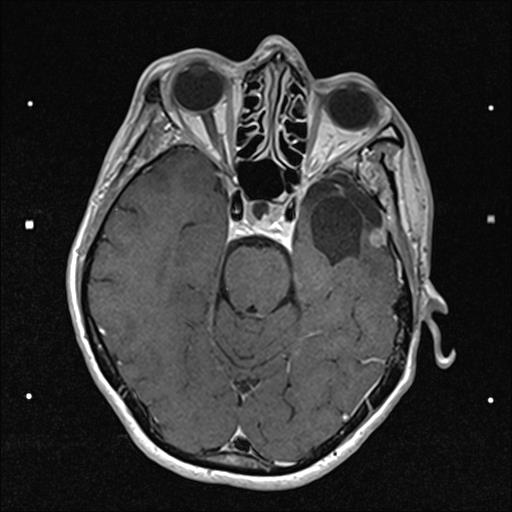

30.03.2017

OP - Krankenhaus Bremen-Mitte

Neurochirugie

Resektion des Keilbeinflügelmeningeoms links